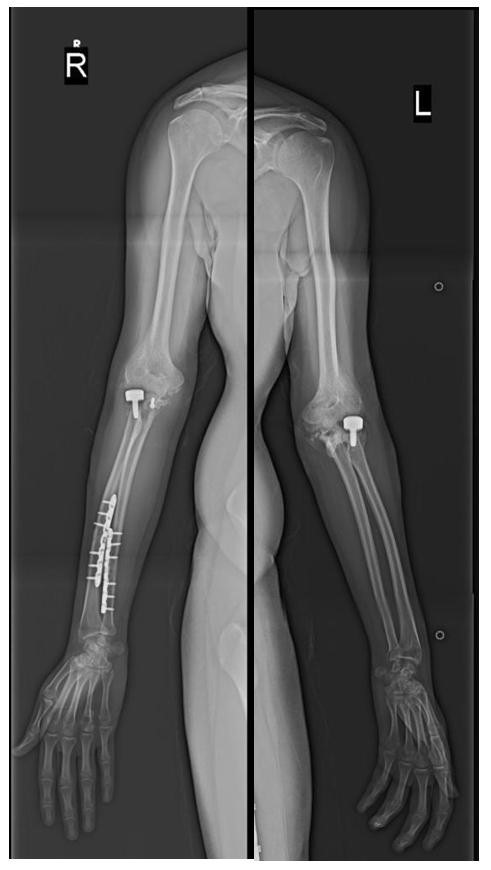

A Rare Clinical Dilemma: Humeral Shaft Fracture in a Full-Term Pregnant Patient – A Case Report with Review of Literature

Laxman Choudhary , Amandeep Bains , Akshant Chandel , Samarjanki Rymbai , Amir Suhail , Debdeep Majumdar

………………………………p.178-184